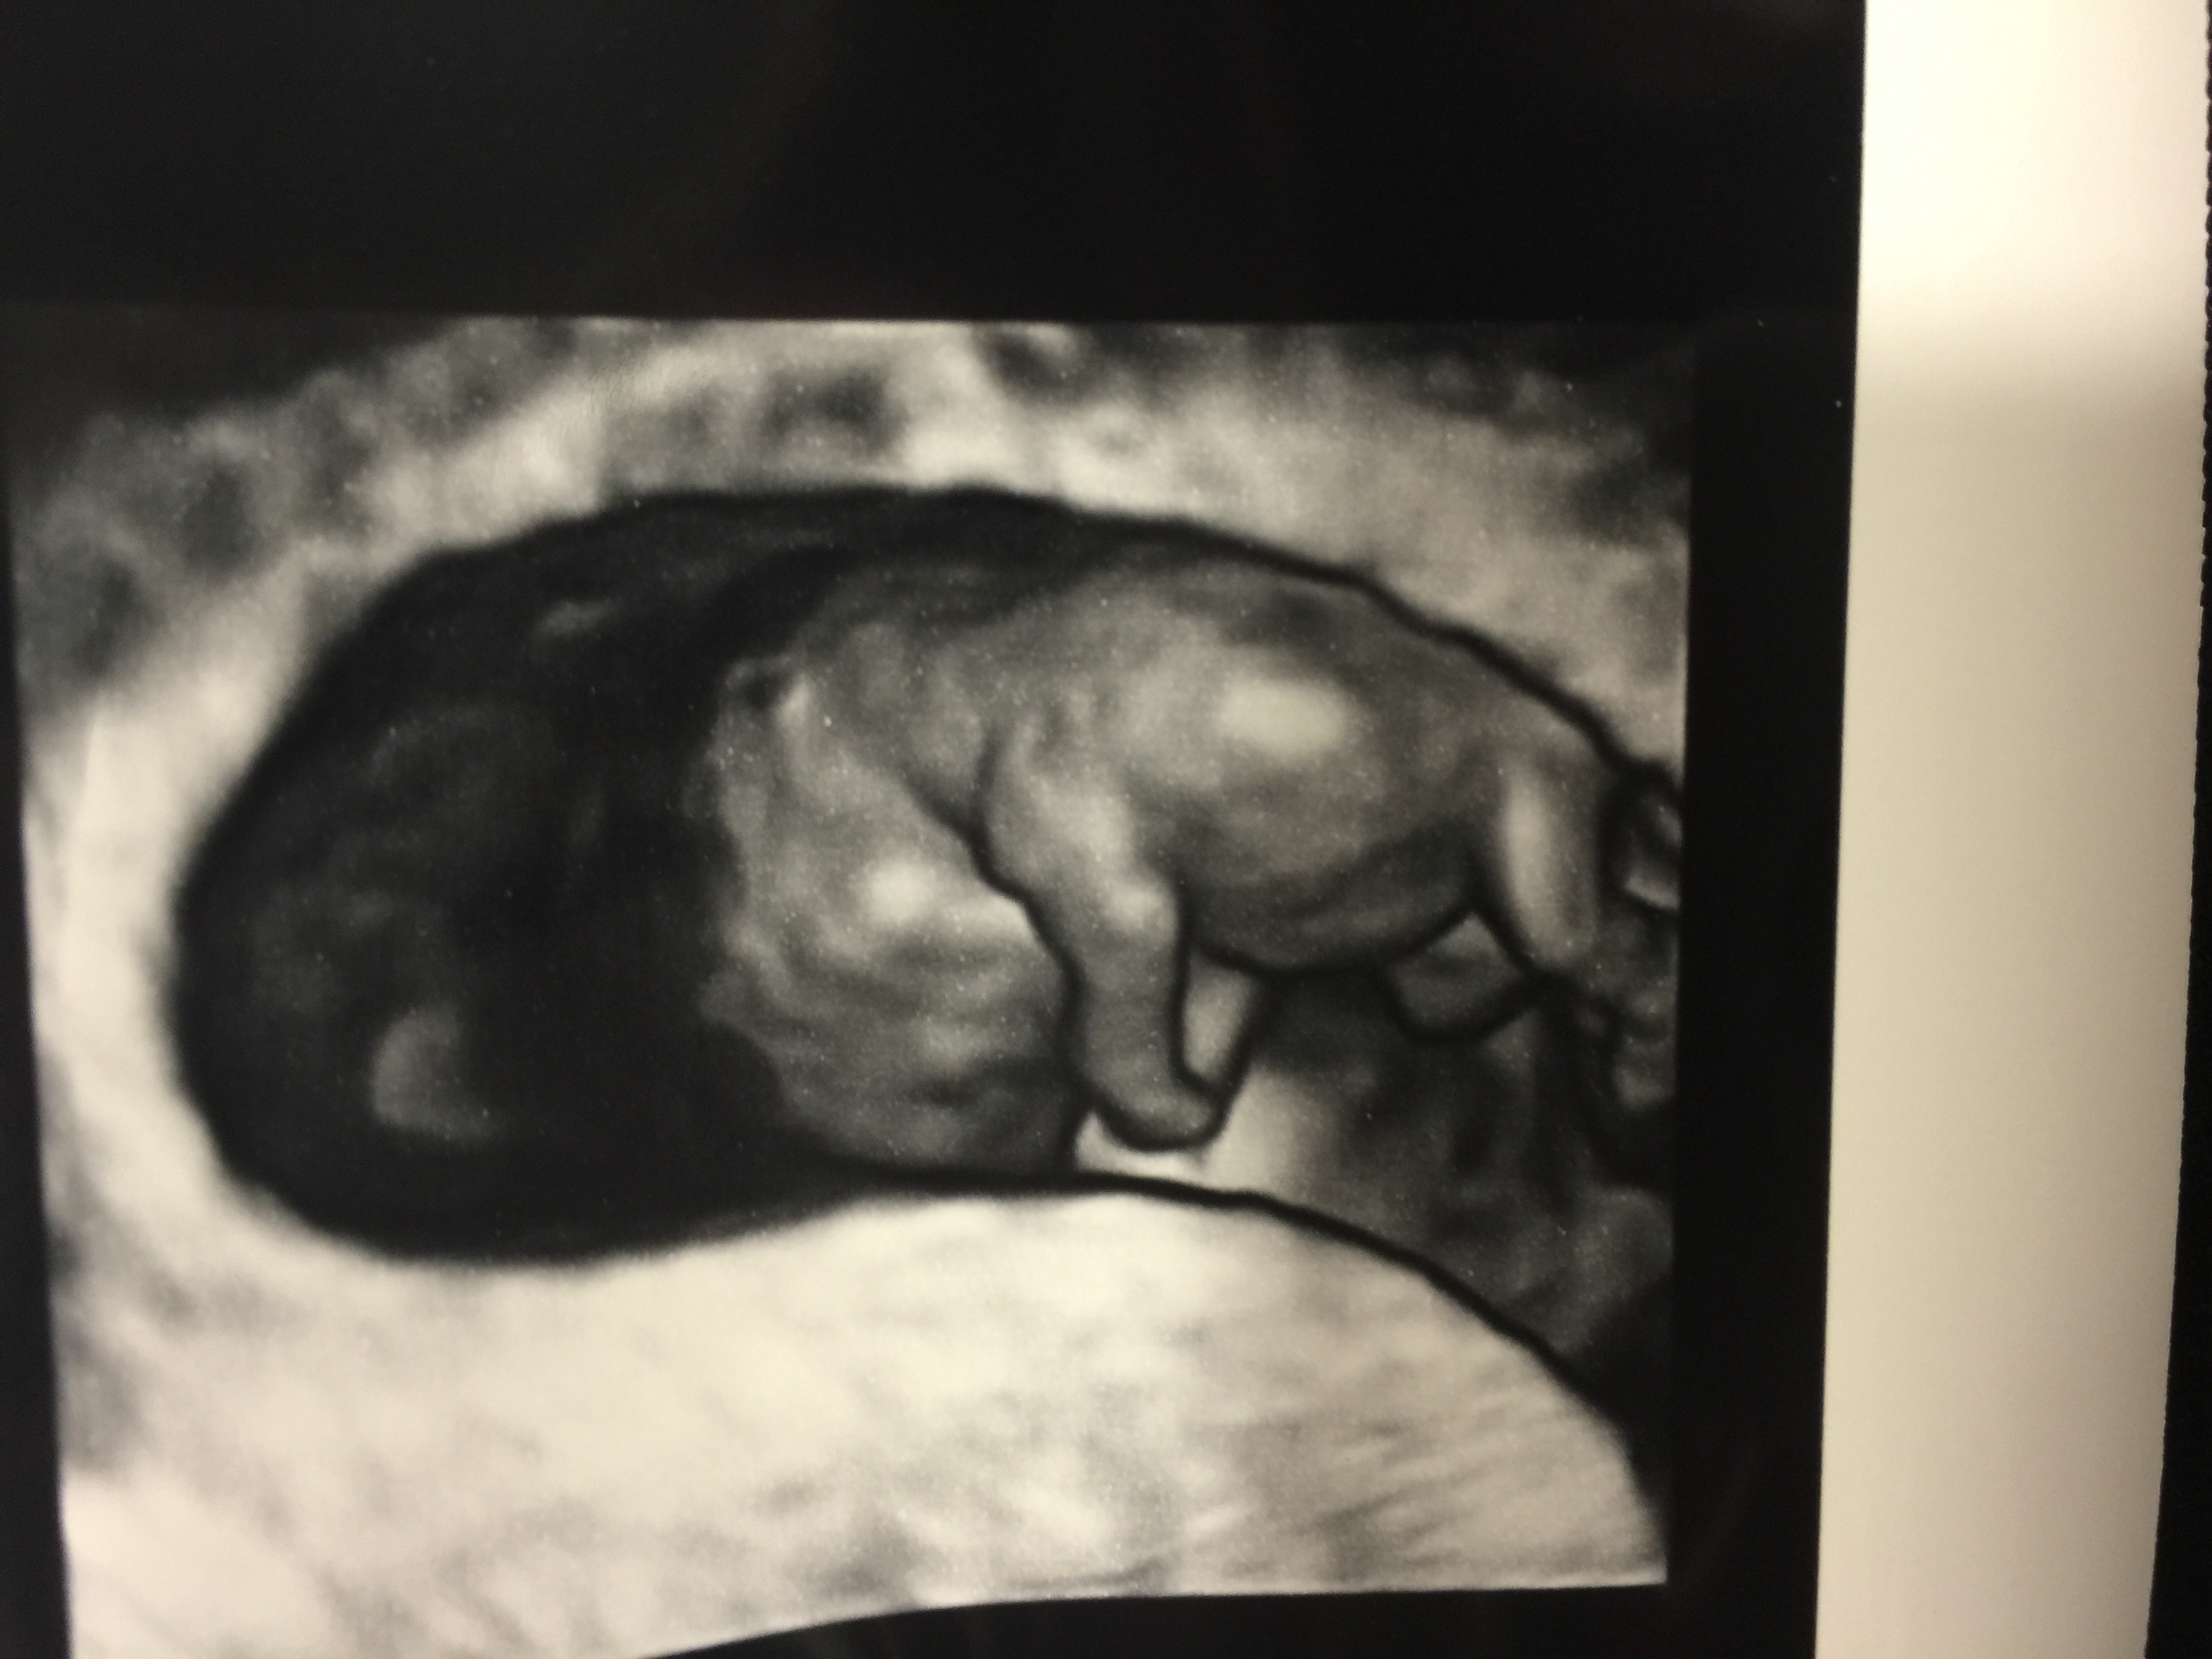

FTM! So excited to see how much my little gummy bear has grown in two weeks! 1st pic is at 6w5d, HR 147, and just a little blob with a flickering heart. 2nd & 3rd pics are at 8w5d, HR 176, and looked so much like a tiny baby with bitty arms and legs. Doc says baby is healthy and quite a dancer, it was moving and waiving all over the place. What a blessed moment to see!